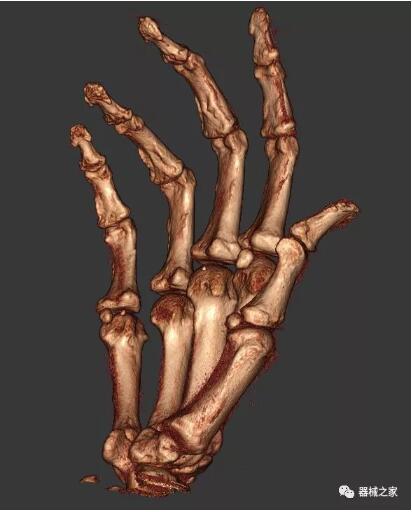

另外一款被稱為世界上最小的CT,它的重量僅300磅,不僅能夠掃查足部,還可以檢查膝蓋和上肢等。

與上面介紹的CT一樣,它同樣具有輻射低、占地空間?。?3*36)的特點(diǎn),隨開隨用(支持直接接入墻上的插座)。

這款CT使用非常方便,通過上下移動(dòng)保持與患者的手臂或者雙腿齊平,掃描快速,僅需要30秒左右就可以完成掃查。

以上介紹的CT均來自國外同一家公司,這些CT均配置了可視化軟件,可以進(jìn)行切片、3D重建以及大型CT附帶的所有典型的操作功能。

以下是這些“特立獨(dú)行”的CT所拍出來的圖像: